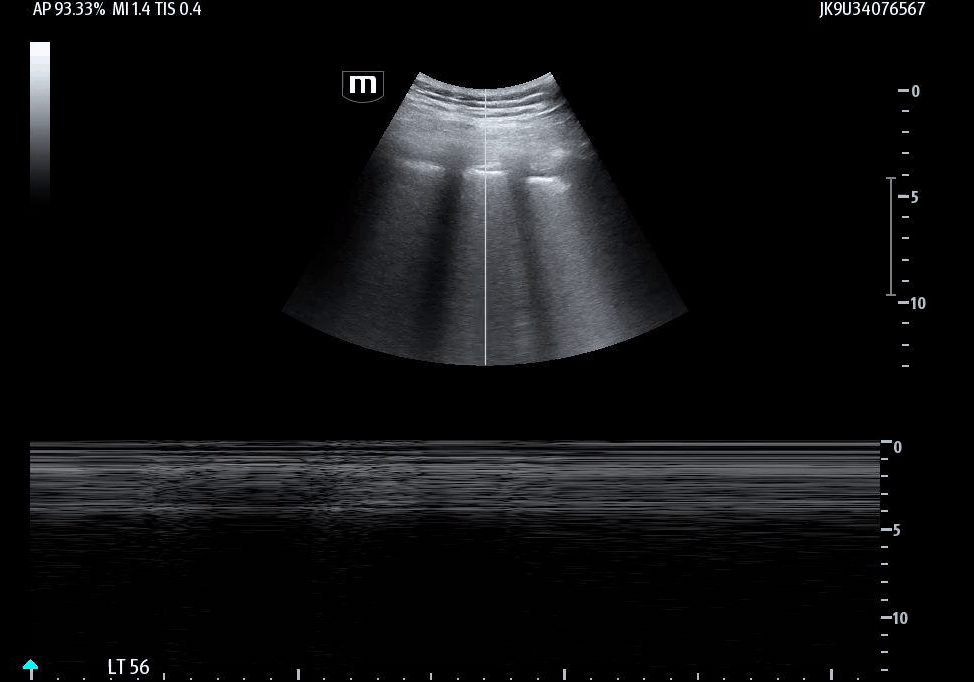

She isn’t crashing—but she isn’t stable either. Luckily, an ultrasound is immediately available. An eFAST exam is performed, revealing the following:

Image 2 confirms this finding using M-mode, demonstrating the classic barcode sign, which is consistent with absent pleural motion.